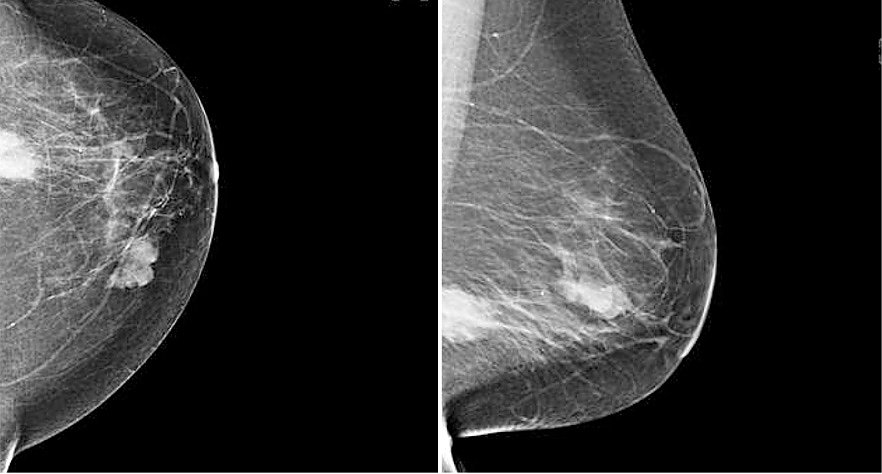

Die Mammografie ist ein Röntgenverfahren, das unter der Nutzung der charakteristischen Strahlung Schwächungsbilder der Brustdrüse erstellt, was üblicherweise in 2 Ebenen erfolgt (sog. CC und MLO-Aufnahme). Die Nutzung direkt-digitaler Systeme ermöglicht hier eine substantielle Reduktion der Strahlendosis von bis zu 40% im Vergleich zu Geräten, die erst im Nachgang ein digitales Bild erstellen oder analog verbleiben. Wir haben ein selenbasiertes Mammografiegerät in der Anwendung als einzigem entsprechend hochwertigen System in Nordthüringen und können so sehr dosissparend arbeiten. Außerdem sind bei uns 4 Röntgenassistenten nach entsprechenden Kursen als Mammafach-MTRA zertifiziert. Wir sind Partner verschiedener Brustzentren und führen im Jahr ca. 1500-2000 Mammografien durch im stationären und ambulanten Bereich. Alle Frauen mit einem Überweisungsschein und einer entsprechenden Indikation (beispielsweise einem Tastbefund oder einseitigen Schmerzen). Ein Mammakarzinom kann als Verdichtung strahlenförmig imponieren, aber auch als vielgestaltig gruppierter Mikrokalk (polymorpher Mikrokalkcluster) sowie in seltenen Fällen als Architekturstörung (siehe Beispielbilder). Ergänzend zu einer Befundung durch 2 Radiologen werden bei uns auch computerunterstützende Systeme verwandt, um eine zusätzliche Analysemöglichkeit zu entwickeln. Über diese Problematik wurden schon zahlreiche Publikationen von Prof. Malich verfasst.